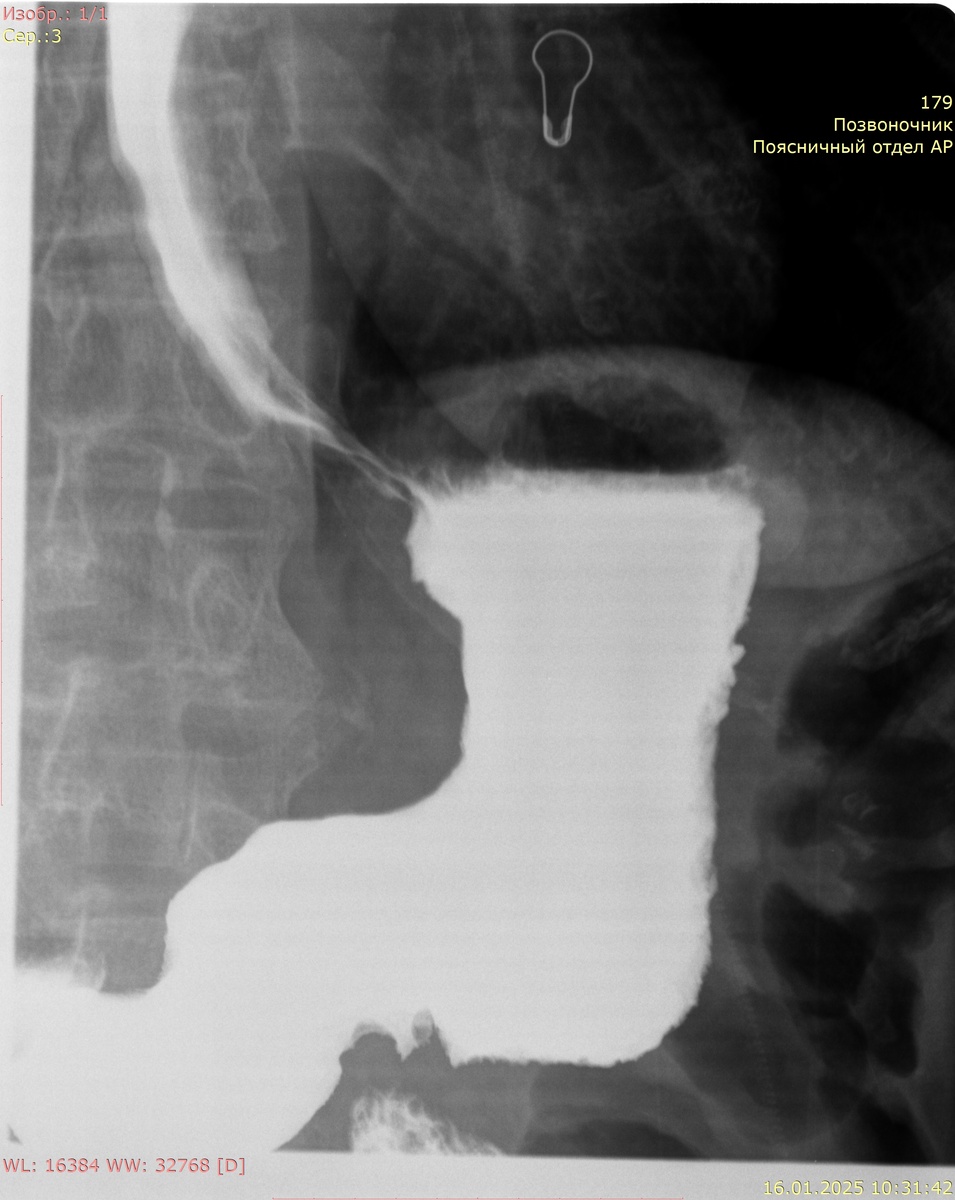

Процесс Проведения Исследования

Исследование проходит следующим образом: после приема раствора бария, пациент располагается на специальном столе, который может изменять свое положение. Это необходимо для получения рентгеновских снимков из различных углов и наблюдения за тем, как барий проходит через пищеварительный тракт. Врач делает снимки на различных этапах, и вся процедура может длиться от 30 минут до 1 часа в зависимости от индивидуальных особенностей пациента и задач исследования.

Затем пациент приходит на снимок каждые 3 часа и врач оценивает положение контраста в кишечнике.